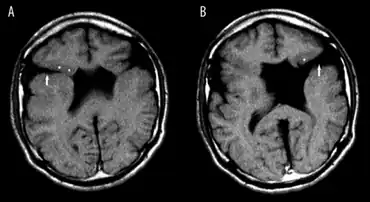

Schizencephaly (from Greek skhizein 'to split', and enkephalos 'brain')[1][2] is a rare birth defect characterized by abnormal clefts lined with grey matter that form the ependyma of the cerebral ventricles to the pia mater. These clefts can occur bilaterally or unilaterally. Common clinical features of this malformation include epilepsy, motor deficits, and psychomotor retardation.[3]

Schizencephaly can be distinguished from porencephaly by the fact that in schizencephaly, the fluid-filled component is entirely lined by heterotopic grey matter, while a porencephalic cyst is lined mostly by white matter. Individuals with clefts in both hemispheres, or bilateral clefts, are often developmentally delayed and have delayed speech and language skills and corticospinal dysfunction. Individuals with smaller, unilateral clefts (clefts in one hemisphere) may be weak or paralyzed on one side of the body and may have average or near-average intelligence. Patients with schizencephaly may also have varying degrees of microcephaly, Cognitive impairment, hemiparesis (weakness or paralysis affecting one side of the body), or quadriparesis (weakness or paralysis affecting all four extremities), and may have reduced muscle tone (hypotonia). Most patients have seizures, and some may have hydrocephalus.[4]

- Radiological methods like computed tomography (CT) and/or magnetic resonance imaging (MRI) - unilateral or bilateral clefting of the brain.